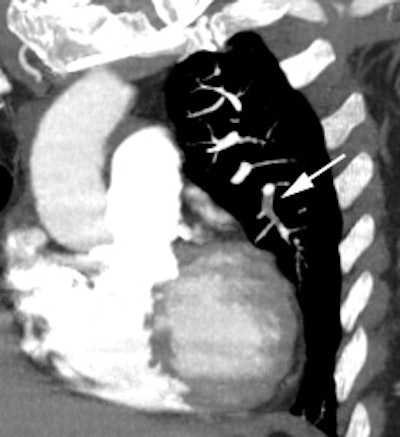

Intermediate probability scan for pulmonary embolism: The patient shown below had a single large segmental perfusion defect in the superior ligular segment of the left upper lobe. Further evaluation was recommended to exclude a pulmonary embolism. A CT PE study confirmed the presence of a PE in this segment. No other emboli were identified. |